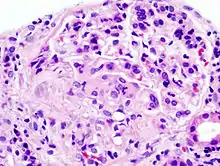

| Histopathological image of crescentic glomerulonephritis in a person with MPO-ANCA positive rapid progressive glomerulonephritis. Hematoxylin & eosin stain. | |